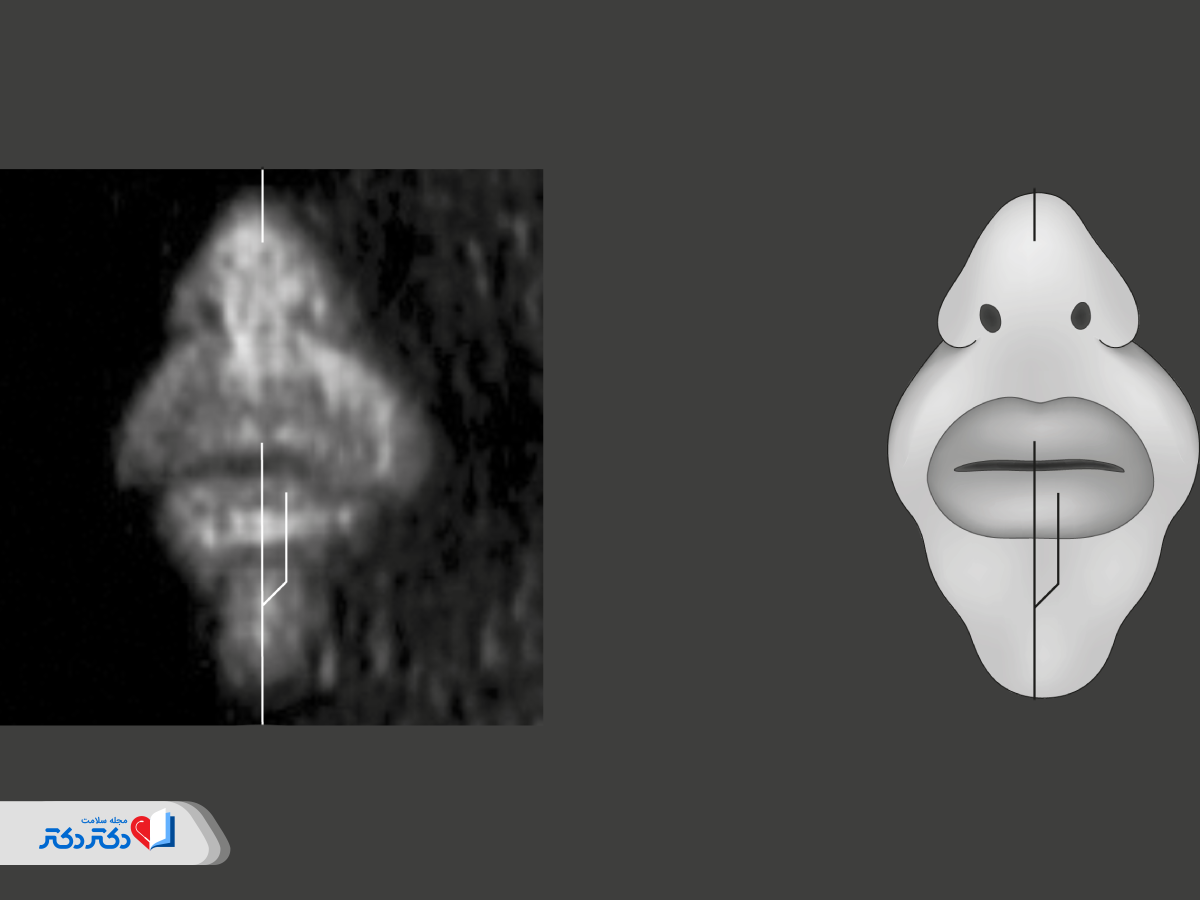

صورت

اگر جنین در موقعیتی مناسب قرار گرفته باشد؛ پزشک متخصص ممکن است شکافلب را بهخوبی تشخیص دهد. اما بهندرت میتوان شکافکام را در سونوگرافی آنومالی اسکن تشخیص داد.

طبق گزارشهای بنیاد شکافکام، شکافلب و شکافکام جزو چهارمین نقصهای مادرزادی شایع در جهان هستند؛ بههمیندلیل نیز تشخیص آنها اهمیت پیدا میکند.

حین بررسی موارد بالا، پزشک وضعیت چانه، بینی و چشمهای جنین را نیز بررسی خواهد کرد.